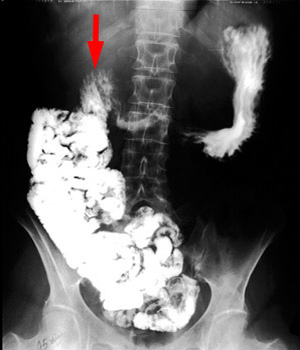

When

suspecting malrotation, an upper GI series would best show the abnormal

position of the ligament of Treitz. |

| Cecum is in an abnormal location in the mid pelvis. | The duodenal-jejunal junction is to the right of the spine, and most of the small bowel is on the right side of the abdomen. |